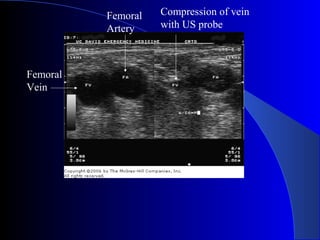

Femoral

Vein

Artery

Compression of vein

with US probe

Ultrasound-Guided CentralUltrasound-Guided Central VenousAccessVenous Access  Becoming standard of care  Vein is compressible  Vein is not always larger  Vein is accessed under direct visualization  Helpful in patients with difficult anatomy